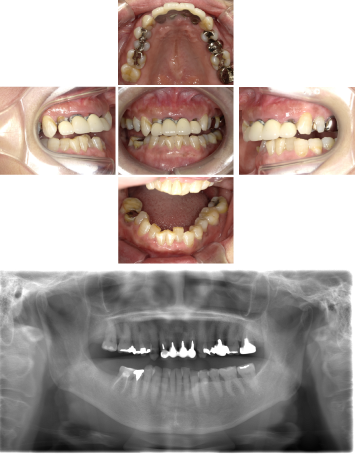

50代 インプラント治療(右上3左上3のみGBR)

| 年代・性別 | 50代・男性 |

| 主訴 | 入れ歯が合わず毎日ヨーグルトしか食べることができないので、しっかり咬めるインプラントにしたい。 |

| 部位 | 右下⑦⑥5④ 上顎③2①①2③ 左下67 |

| 治療期間 | 約9ヶ月 |

| 費用 | ¥4,273,500(税込) |

| 副作用・リスク |

|